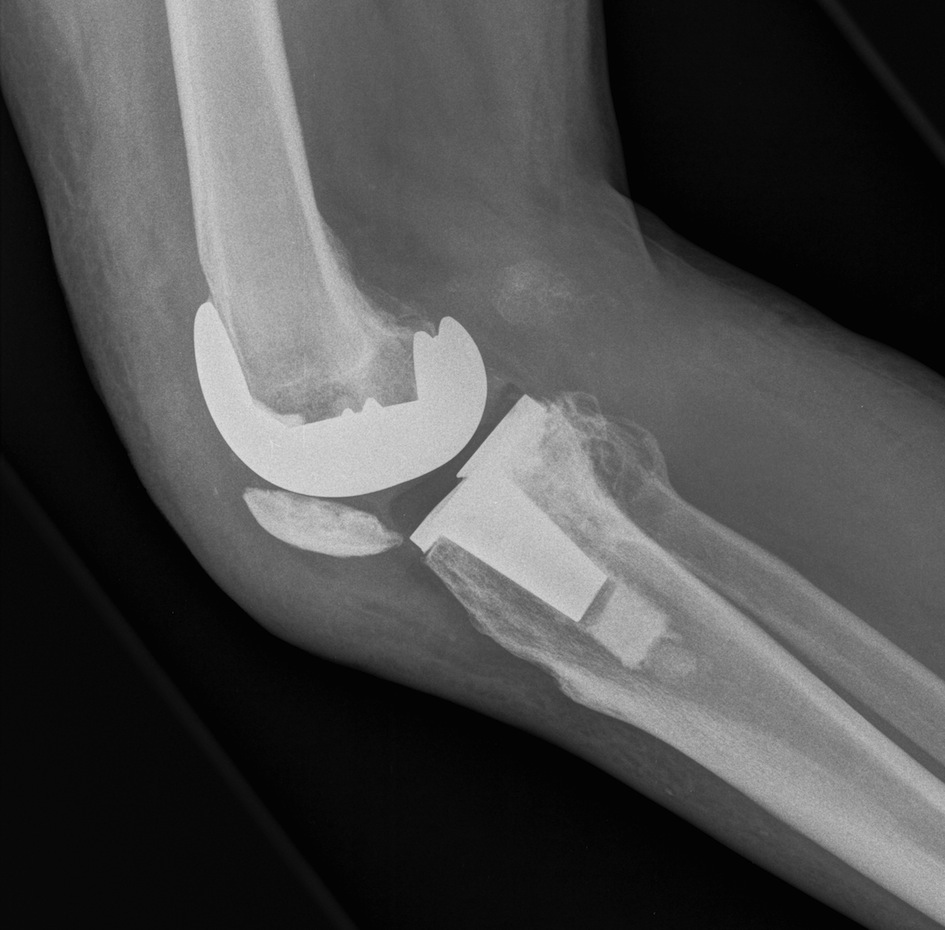

Surgical options

1. Lateral release + Patella resurfacing

2. Tibial tuberosity transfer +/- MPFL reconstruction

Barber et al Arthroscopy 2008

- 91% successul in eliminating instability in 35 knees

- used Elmslie Trillat